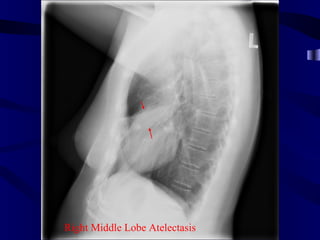

Indistinct Right Heart Border

Right Middle LobeAtelectasis